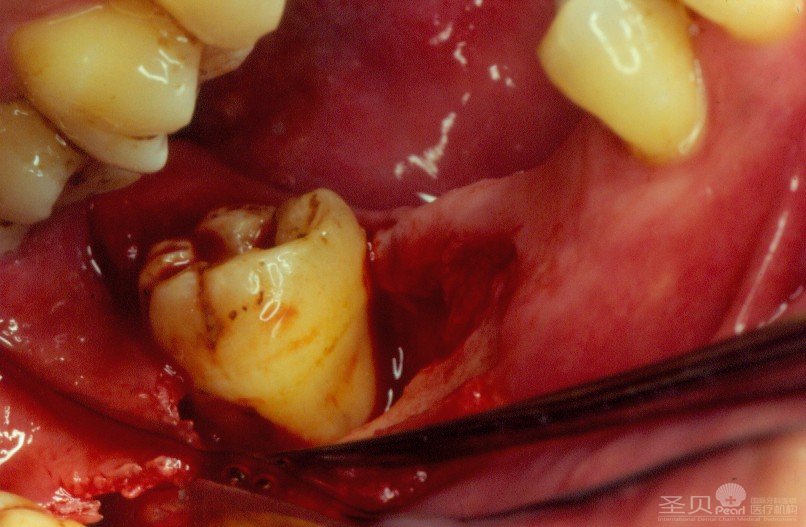

牙龈出血,常见的是患牙龈炎和牙周炎病人。这些病人由于不经常刷牙,或由于刷牙的方法不正确,在牙龈边缘的地方产生牙石。牙石是一种坚硬的石灰样物质,对牙龈有刺激作用,能引起牙龈发炎、肿胀、充血,轻者在刷牙、吮吸、咬硬物或剔牙时出血,重者在轻微刺激或没刺激时也会出血。如发炎、高烧致牙龈组织的血管结构发生改变,也会造成出血。

5.探诊出血

健康的牙龈在刷牙或探测龈沟时均不引起出血。患牙龈炎时轻触即出血,探诊也出血。探诊后出血是诊断牙龈有无炎症的重要依据。